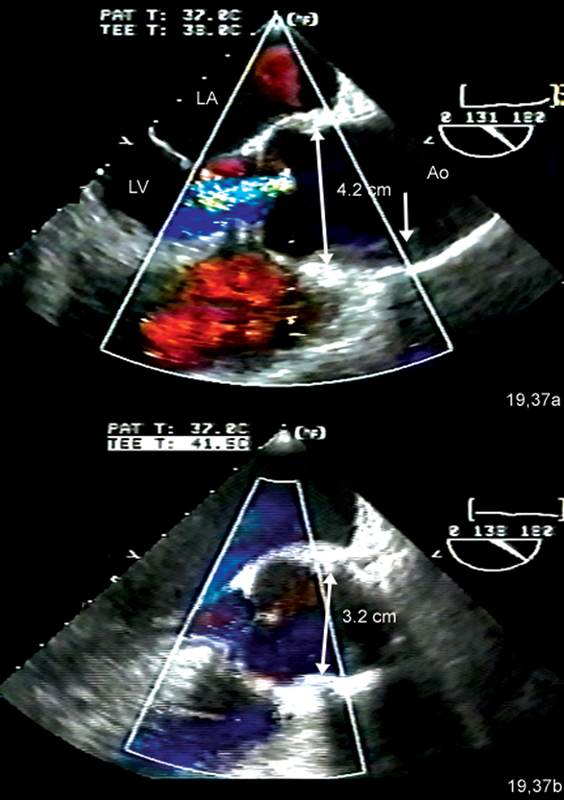

فحوصات تشخيصية لبعض امراض القلب والشرايين التاجية